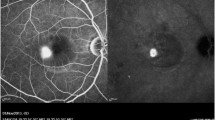

The treatment was started 15-20 minutes after the injection of 25 mg of ICG in 2 cc of 5% glucose solution (Infracyanine SERB), when (a) the hypofluorescent washout of the retinal and choroidal vessels, and (b) the ICG staining of the RPE–Bruch’s membrane complex were visible at ICG angiography (ICGA) [28]. Prior to proceeding with the treatment of the central active leakage site, a test burn was performed either in the nasal mid periphery (Fig. 1a) or on a peripheral active leakage site when present (Fig. 1b) to ensure that no visible or latent retinal burn would result. Each active leakage site was treated with fifty sequential trains of micropulses of 500-ms duration (500 mW power, 10% duty cycle, 0.2 ms “On” time” + 1.8 ms interpulse “Off” time = 2.0 ms), separated by 500-ms pauses, for a total treatment time of 50 seconds.

a ICG angiography (ICGA) 20 minutes after injection, showing the background hyperfluorescence due to the RPE staining and the retinal-choroidal vessels’ hypofluorescence due to the dye wash out. The dark spot under the white arrow is the result of the test run performed on the nasal side. b Late-phase ICGA showing the hyperfluorescent juxtafoveal active leakage site (ALS, red arrow) surrounded by pathologic stained RPE and the test run performed on eccentric ALS (white arrow). The fovea’s position is indicated by the white circle (overlay performed with Topcon ImageNET)

No sign of laser-induced lesion was detectable either ophthalmoscopically or at angiography at any follow-up time in all seven patients, as shown in the post-treatment color retinographies and early (2-week) angiographies (FA and ICGA) of the first patient (Fig. 3). Furthermore, no trace of the treatment was evident at fundus autofluorecence in patients 4 and 7 imaged by mean of HRA2 2 weeks after the treatment (Fig. 4). Six-month angiographies of patients 4 and 6 revealed the lack of any scar due to laser photothermal damage (Fig. 5).

Patient 1: Colour fundus photography (a) and FA showing the active leakage sites before the treatment (b). ICGA without (further dye injection) after the laser treatment: note the two dark spots at the site of the laser treatments (c). Colour fundus photograph (d), fluorangiography (e) and ICG angiography (f) 1 week after the treatment: note the reduction of the retinal serous detachment and the lack of any sign of the laser-induced scar

Patients 4 and 7: fundus autofluorescence at HRA2 before (a,f) and 2 weeks after the treatment (e,j). Active leaking sites at FA (b,g) and at late-phase ICGA: note the hyperfluorescence due to higher dye uptake by pathologic RPE (c,h). Hypofluorescent areas at late phase ICGA (without further dye injection) at the treated leakage sites (d,i)